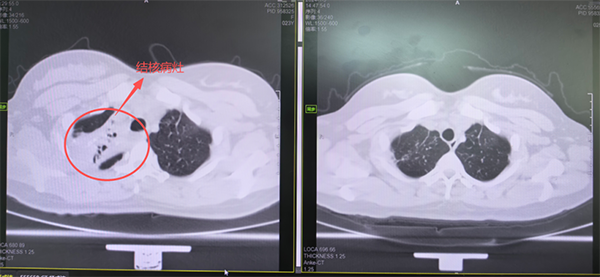

(左:治疗前肺部影像,右:治疗后肺部影像)

“气管通畅,黏膜正常,未见新生物。”历经12次气管镜介入操作与耐心清理,在团队精湛的技术与默契配合下,气道内坏死组织被逐步清除,狭窄气道得以有效扩张。至此,小许的气道梗阻顺利解除,重新恢复了顺畅呼吸,顺利出院。